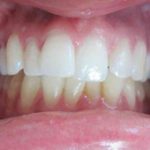

Présentation cas clinique :

Avant traitement

Après traitement